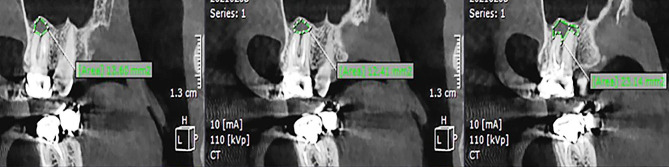

Data on the four dependent variables were recorded: presence of PL, PL volume, presence of CBD, and BPBH. PL was identified as absent when intact periapical bone structures could be detected (diameter of the periapical radiolucency under 0.5 mm), and otherwise as present [25]. In order to evaluate PL volume, the tooth was viewed in the sagittal plane with one-millimeter interslice intervals. The surface area of the PL in each slice was measured using the area tool in the software (Fig. 2). Considering the PL as an asymmetrical 3D object, its volume was measured using the formula presented below, where h represents the interslice interval, and S denotes the surface area of partial frustum bases. The accuracy of this measurement method has been proven in several publications [18, 26, 27].

Fig. 2.

Determining the surface area of the PL in three consecutive slices using the area tool